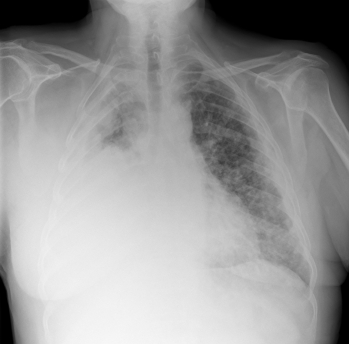

Серия рентгеновских лучей пищевода после того, как пациент выпивает раствор, содержащий барий. Бария пальто и излагается в пищеводе при рентгеновском и могут быть полезны в выявлении рака и других нарушений пищевода.

Типичные осложения:Редко пациенты могут подавиться бария вызывает воспаление легких.